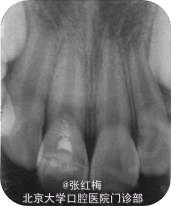

X线示:11、21发育9期,根管粗大,未见明显根折线,根尖周未见病变影,骨硬板清晰,未见牙槽突骨折线;

检查:11充填体完好,叩(-),不松,龈未见异常,X线:11根尖继续形成中,根周膜清 晰;

检查:11粘接断冠完好,叩(-),不松,龈未见异常,冷测有感觉,无疼痛;X线:11根 尖继续

形成中,根周膜清晰